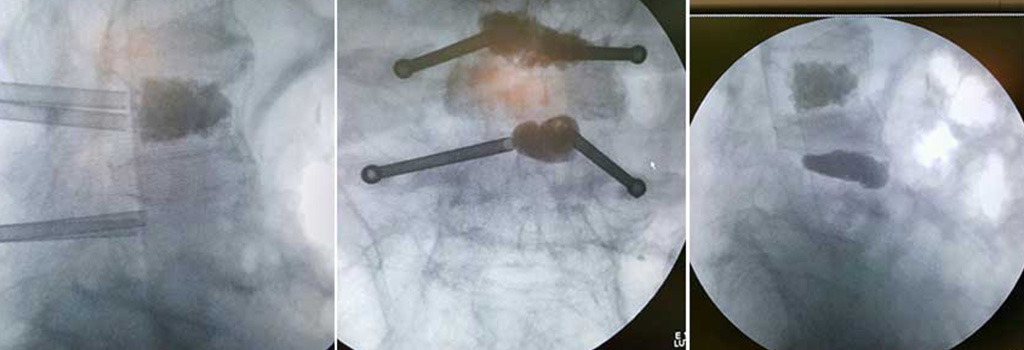

Χρησιμοποιούμε ακτινοσκοπική καθοδήγηση για να εισάγουμε δια μέσου βελόνας ένα μπαλόνι στο σπονδυλικό κάταγμα, το οποίο εκτεινόμενο ανατάσσει το κάταγμα και δημιουργεί μια κοιλότητα μέσα στον Σπόνδυλο. Η ενίσχυση των σπονδύλων που έχουν υποστεί κάταγμα γίνεται με έγχυση ειδικού σκληρυντικού υλικού στην κοιλότητα όταν το μπαλόνι απομακρυνθεί. Η χειρουργική τομή είναι περίπου 0,5 εκατοστά.

Ασθενής 76 Ετών προσήλθε με έντονους πόνους Οσφύος στα πλαίσια κατάγματος Ο1 και Ο3 .

Αντιμετωπίστηκε με Διαδερμική Κυφοπλαστική στους παραπάνω σπονδύλους.